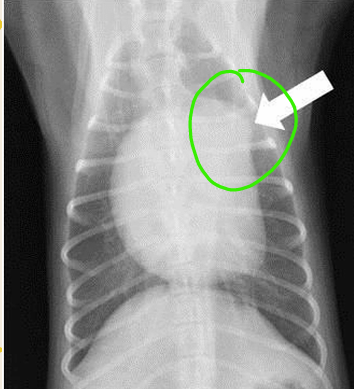

VD

arrow pointed the THYMUS